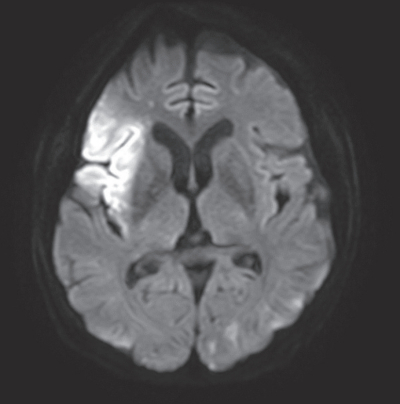

On physical examination, consciousness level was GCS E4V4M6, blood pressure 164/82mmHg, pulse rate 96/min and irregular. Neurological examination was unremarkable except for left hemiplegia. No carotid bruit was heard on either side. Brain MRI is shown in the figure.